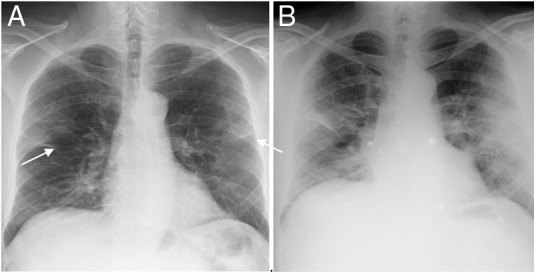

Finally, a third quantification system (8) divided both lungs into 8 lung fields, as reflected in Fig. 2 . The involvement of 1–3 fields implied a mild degree; this was deemed moderate when 4–6 fields were involved, and severe if 7 or 8 fields were affected.

Figure 2.

Posteroanterior chest X-ray demonstrating division into 8 lung fields by three horizontal lines (quantification system 8). Upper pulmonary field (from vertices to the upper border of the aortic knob), mid-hilar pulmonary field (from aortic knob to hila), mid-paracardiac pulmonary field (from hila to lower third of the cardiac silhouette), lower pulmonary field (from lower third of cardiac silhouette to costophrenic sinuses).

An alveolar pattern was found in 22.3% of the initial X-rays (Fig. 4 ), linear opacities (mainly lamellar atelectasis) in 47.2%, and both findings in 9.8% of the cases. The interobserver agreement regarding linear opacities corresponded to kappa = 0.798 and 90.3% correlation. Regarding alveolar involvement, it was found to be kappa = 0.943 and 98.86% correlation (Table 1 ).

Figure 5.

48-year-old man with COVID-19-associated pneumonia. A) Posteroanterior chest radiograph showing bilateral and linear alveolar opacities of peripheral distribution (arrows). The score is 3/6 fields and 4/8 fields, which correspond to moderate involvement in the three systems 6A, 6B and 8. B) The anteroposterior X-ray performed 72 h later shows a worsening of the radiological pattern with more extensive involvement and pulmonary consolidations. Quantification: 5/6 fields and 6/8 fields, corresponding to severe involvement in systems 6A and 6B, and moderate in system 8.